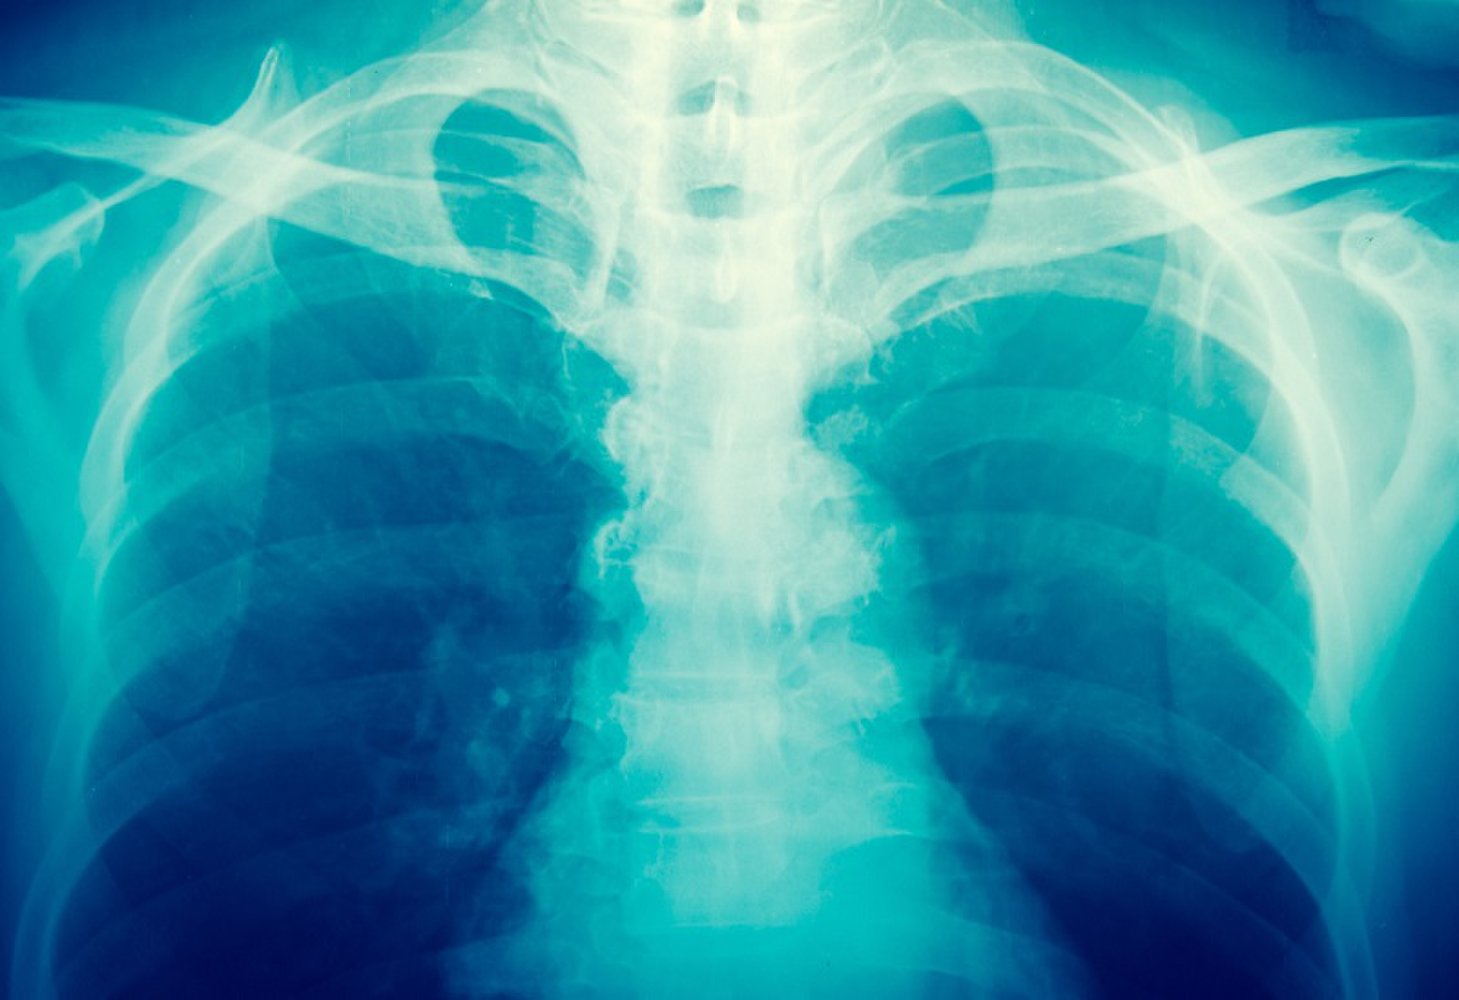

Рентгеновское излучение фото для презентации - 84 фото